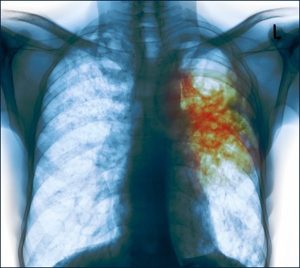

Mik a fő diagnosztikai módszerek?

A fő diagnosztikai eszközök gyanús TB közzé tartoznak:

- mellkas röntgen;

- A CT-vizsgálat;

- radiográfiai;